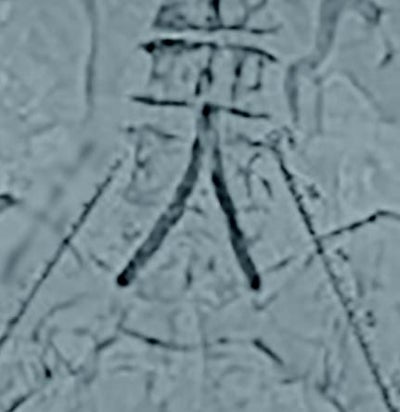

両側橈骨動脈より順行性に両側CIAにガイドワイヤーを通過させた。病変は偏心性石灰化でバルーン拡張により血管破裂のリスクがあることからVBXステントグラフト7.0 × 79 mm(6 Fr)を選択した。両側橈骨動脈からのアプローチにより(図4)スコアリングバルーンによる前拡張後(図5,6)、VBXステントグラフトを留置し(図4,7)、後拡張として高耐圧バルーン8.0 × 40 mmでキッシングバルーンテクニック(KBT)を行った(図8)。この際に迷走神経反射により心拍数が39回/分となったことから、これ以上の径での拡張は危険と判断し、手技を終了した。VBXステントグラフト留置後(図9)と術後造影(図3)では良好な血流が確認された。

足関節上腕血圧比(ABI)は術前は右0.97左0.61が、術後は右1.15左1.11へと改善が確認された。